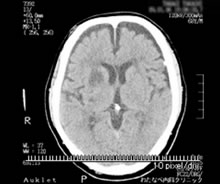

脳出血や脳梗塞は、ある日ある時突然に、脳の血管が切れて出血したり、詰まってしまう(梗塞)ことで、色々な障害が生じます。障害された場所により症状が異なります。同じ側の手足がマヒしたり、感覚障害(シビレや痛み)がみられたりします。また、呂律が回らなくなったり(構音障害)、言葉が理解できるのに話せなくなる(失語症)ことや、ものが二重に見えるなどの様々な症状を呈します。診断は急激な発症かどうかということを考慮し、神経学的診察所見および頭部CTなどの画像診断から判断します。